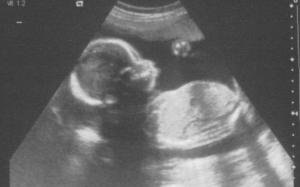

But it didn’t stop there. So we’re in the ultrasound room, and the poor ultrasound tech is trying to take measurements of the kid; you know, making sure the kidneys, bladder, stomach etc are all on track, that all four heart chambers are functioning, that he isn’t growing a second head, that his cerebellum isn’t in the wrong place, etc. But is my darling parasite cooperating? No. Instead, he is tearing around my uterus like a mad animal, hitting everything in his path and flashing his junk whenever he gets the chance. Awesome. Frustrated, the ultrasound tech tells me to get up and dance around a bit, to see if that gets him to move to a more suitable position. So I dance around like a fool in the middle of the office and sure enough he moves, but not where he’s supposed to. Now he’s facing the camera and hiding everything that needs to be measured. Sigh. We were there three times as long as last time. And when we left, he continued to dance around in my uterus for another hour. He’s got spunk, I’ll give him that.